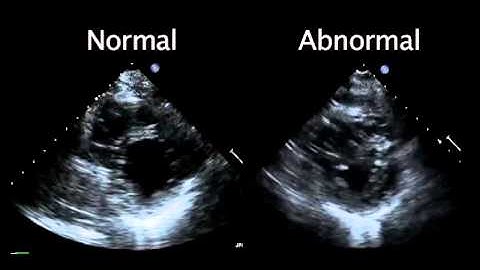

Normal Echo vs Abnormal Echo | Heart Attack | Naresh Rathod #heartattack #humanheart